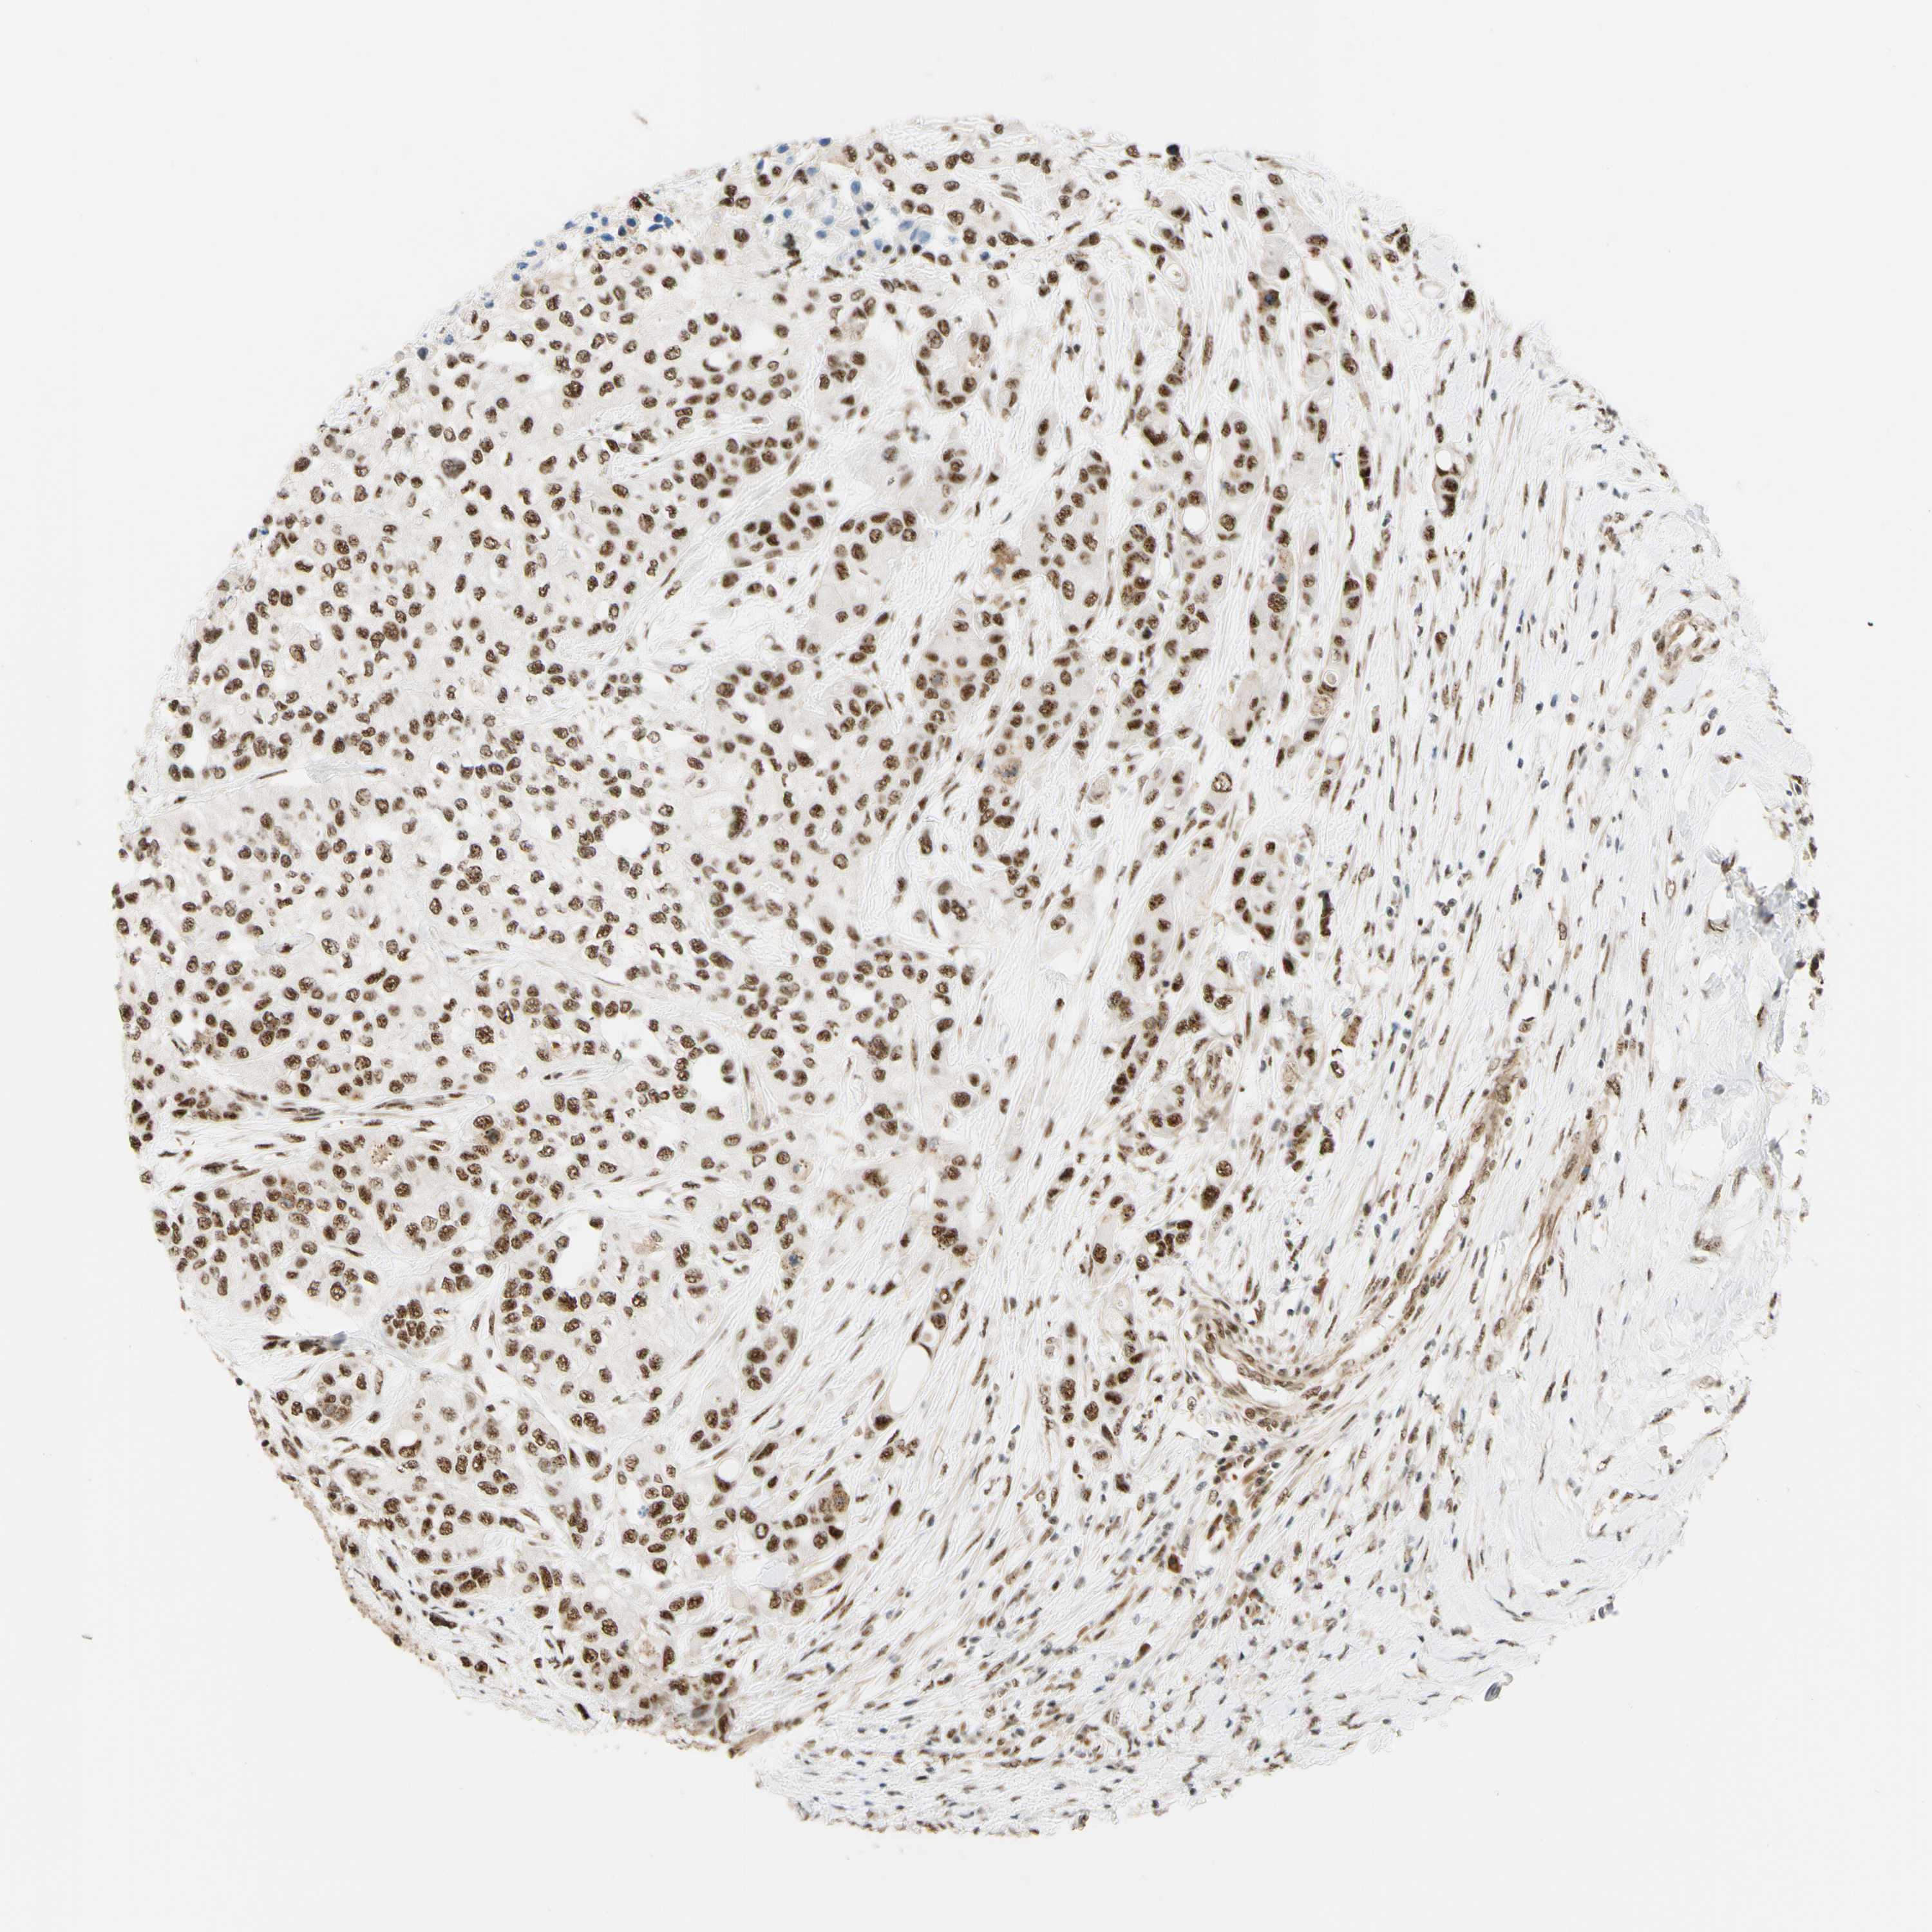

UROTHELIAL CANCER - Protein expressioni

A mouse-over function shows sample information and annotation data. Click on an image to view it in a full screen mode. Samples can be filtered based on level of antibody staining by selecting one or several of the following categories: high, medium, low and not detected. The assay and annotation is described here.

Antibody stainingi

Antibody staining in the annotated cell types in the current human tissue is reported as not detected, low, medium, or high, based on conventional immunohistochemistry profiling in selected tissues. This score is based on the combination of the staining intensity and fraction of stained cells.

Each image is clickable and will lead to virtual microscopy that enables deeper exploration of all samples and also displays staining intensity scores, fraction scores and subcellular localization as well as patient and tissue information for each sample.

Antibody HPA011352

Antibody CAB012273

Staining

High

Medium

Low

Not detected

Intensity

Strong

Moderate

Weak

Negative

Quantity

>75%

75%-25%

<25%

None

Location

Nuclear

Cytoplasmic/membranous

Cytoplasmic/membranous,nuclear

Urothelial carcinoma, Low grade

Urothelial carcinoma, High grade